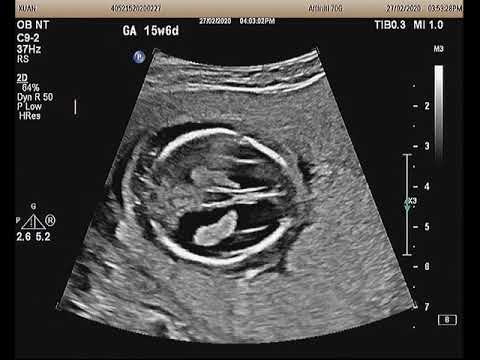

Những điều mẹ bầu cần lưu ý khi thai bị giãn não thất bên

Trẻ em bị giãn não thất thường với triệu chứng: vòng đầu tăng nhanh, đau đầu, chán ăn, hay ói mửa, thay đổi hành vi và tính cách, thay đổi thói quen, suy giảm trí tưởng, mất tập trung, mỏi mệt, thất đ